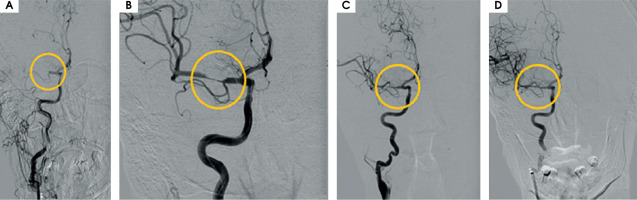

After MT the blood flow in the artery was returned with TICI 3 (Figure II). The day after the MT, control CT showed haemorrhagic foci (Figure III). The patient returned to the ICCU three days later. His neurological status was the same as before the MT of RMCA. In repeated CTs of the brain, haemorrhagic foci were still present (Figure IVA). In the following days of hospitalization, the resolution of haemorrhagic and evolution of ischemic cerebral lesions were observed (Figure IVB).

Figure II

A) Right middle cerebral artery (RMCA) occlusion: 7 mm from its ostium from the right internal carotid artery – TICI 0. B) Mechanical thrombectomy performed twice using stent retriever Solitaire X 6 × 40 mm – branches of RMCA are opened, still present thrombus which narrowing lumen of RMCA in segment M1. C) After first aspiration of thrombus (catheter – ACE68). D) After second aspiration of thrombus – final result TICI 3